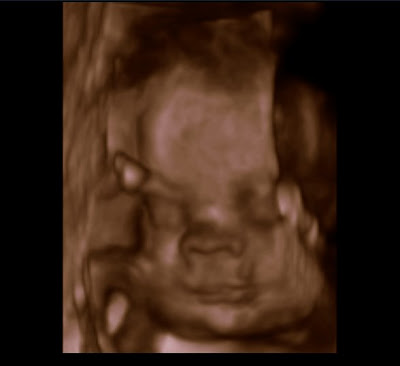

I went in for my regular check-up today. My doctor does a 3D ultrasound at this stage and gave us a CD of the pictures. I thought it would be fun to try out the Picasa slide show feature and post them this way on our blog. Ella and Tim came with me and we really enjoyed seeing the baby together. Ella said “It’s a baby!” and “Cute” when she looked at the monitor. These ultrasounds are so amazing as you see your baby open and close his mouth and his features are so distinct.

| 3D Ultrasound Pictures |